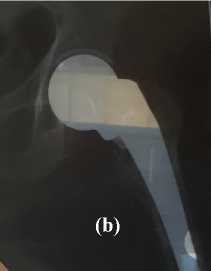

Gambar 3: a) Pasca AMP dengan skor HHS tertinggi; b) Pasca AMP dengan skor HHS terendah

Nilai rerata HHS dari sampel yg diteliti yaitu 88 dengan pembulatan ke atas, dengan nilai terendah yaitu 77 dan tertinggi sebesar 96.

Bila melihat hasil HHS dari semua sampel, dengan sebagian besar (62,5%) menunjukan hasil yang memuaskan dan tidak ada hasil operasi yang masuk katagori hasil buruk (Tabel 2). Hal ini merupakan pencapaian yang baik terlebih melihat rerata HHS sampel sebesar 88 dengan katagori hasil yang baik.